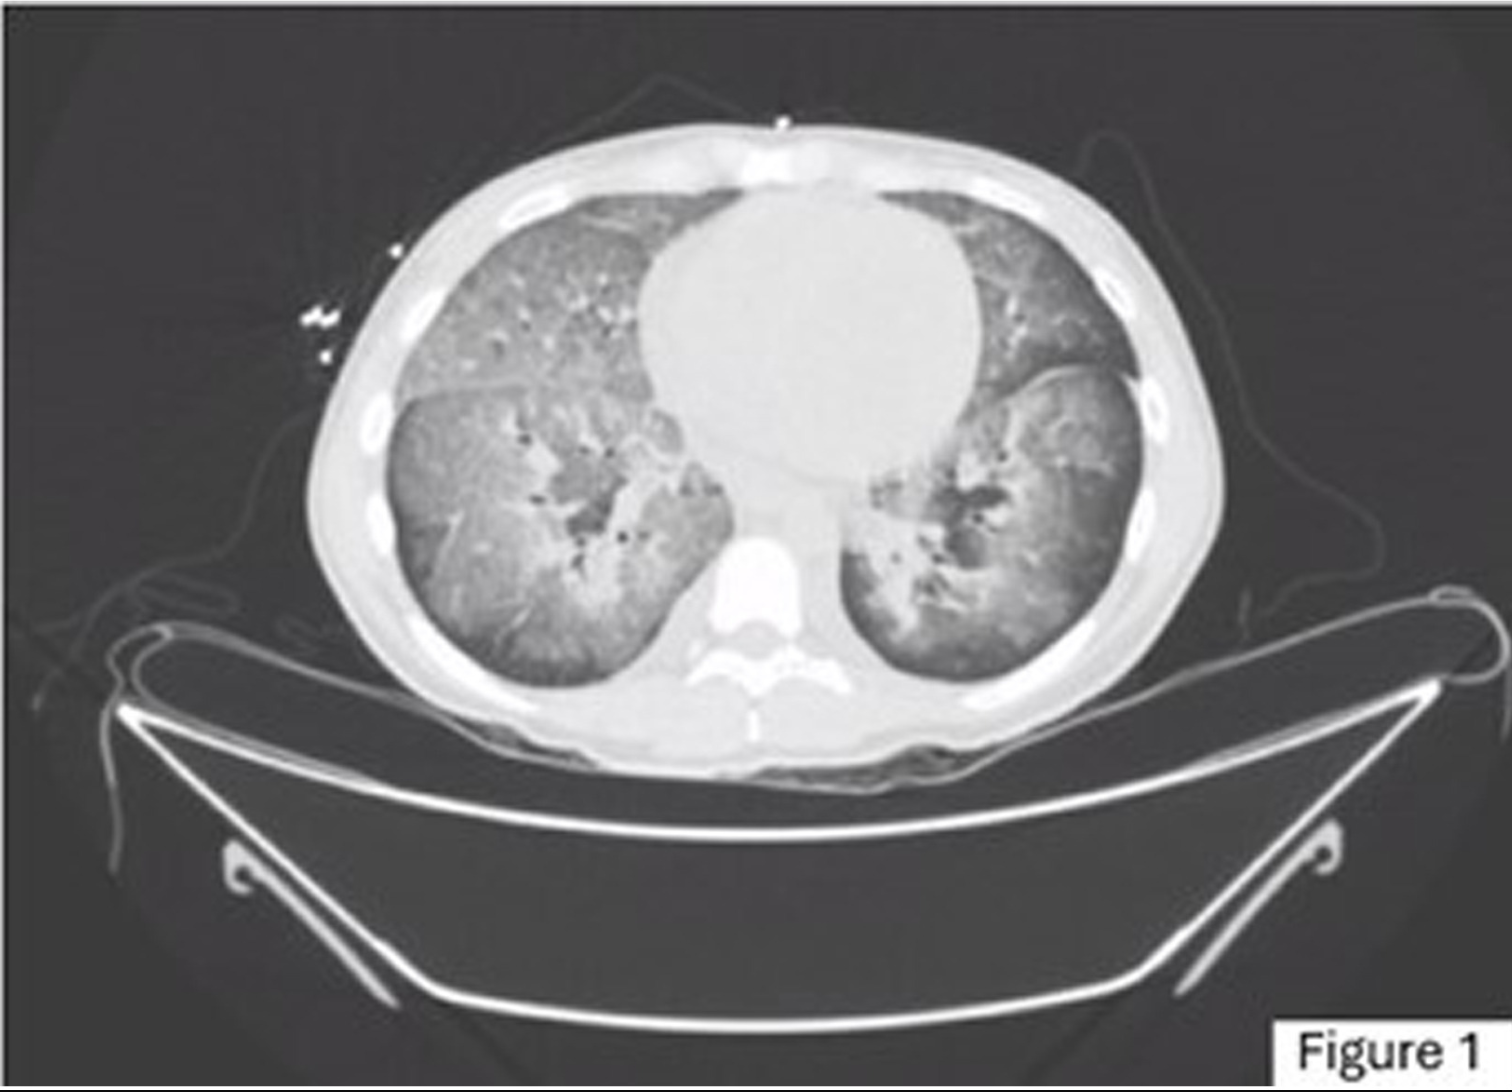

图1. 胸部CT提示弥漫性肺泡出血

实验室检查结果显示:血清肌酐(SCr)19.6 mg/dl,肾小球滤过率(GFR,CKD-EPI)2.3 ml/min/1.73m²(CKD-EPI 公式计算),血尿素氮(BUN)160 mg/dl,血钠138 mmol/L,血钾7 mmol/L,补休C3为106 mg/dl,补休C4为24.1 mg/dl。免疫学检查中,抗肾小球基底膜抗体(Anti-GBM)、抗双链DNA抗体(Anti-dsDNA)、P-ANCA和C-ANCA均为阴性。尿液分析显示红细胞约30个/高倍视野,蛋白30 mg/dl。血气分析提示阴离子间隙增高型代谢性酸中毒。